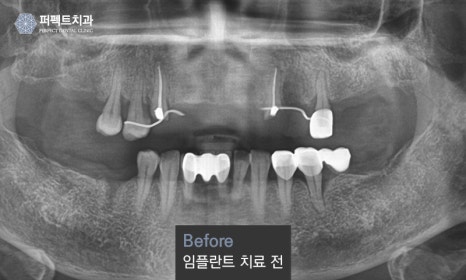

위 임플란트 치료 전/후 사진은 실제 퍼펙트치과 환자분의 전악 임플란트 전,후 사진입니다.

퍼펙트치과 홈페이지 치료전후에 들어가보시면 임플란트, 치아교정, 앞니치료를 받으신 분들의

치료 전/후 사진이 있습니다. 의료법상 로그인을 하신 분들만 보실 수 있으니 참고해주세요 :)